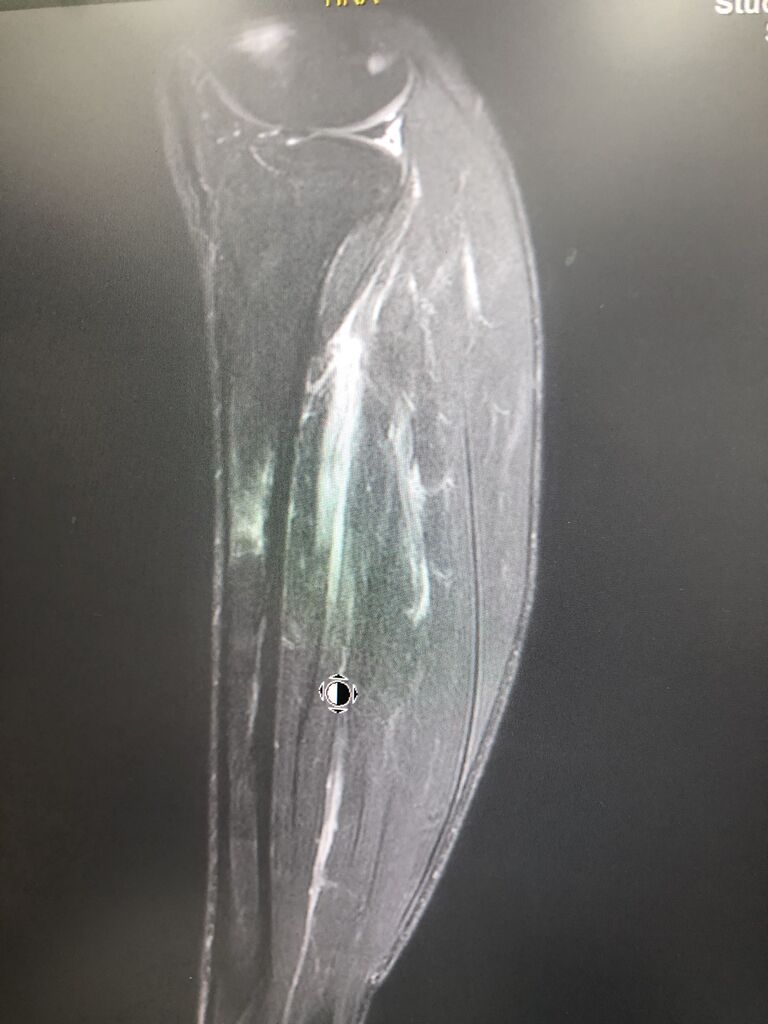

全日本トップランナーも、

疲労骨折あります。

しかし、プロの足は、日常での使い方が

しっかりしているので、

ストレッチ、トレーニングで

早く回復します!